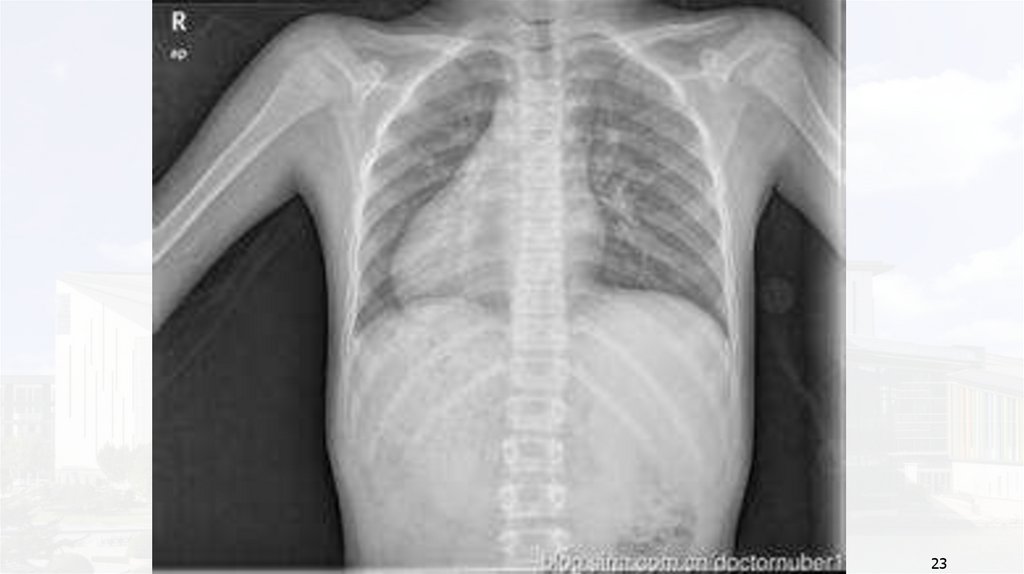

后前位胸片可见肺动脉段明显突出或其高度≥3mm。心尖上翘提示右心室肥大。

21

Case 1

22

23